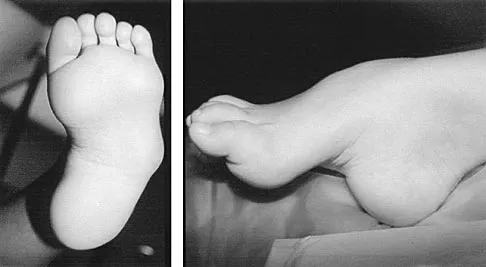

Question 97 High Yield

A 6-year-old girl has the bilateral foot deformity shown in Figure 1. There is no family history of disease. Examination reveals fixed hindfoot equinus, and muscle function testing shows strong posterior tibial function, fair plus anterior tibial function, poor peroneal function, and strong gastrocnemius function. A Coleman block test shows a correctable hindfoot. Nerve conduction velocity studies show diminished function in the peroneal and ulnar nerves on both sides. Pathologic changes found in a sural nerve biopsy include "onion bulb" formation, and DNA testing confirms the presence of a mutation in the MPZ gene, consistent with hereditary motor sensory neuropathy type III (HMSN-III). What is the best course of action?

Detailed Explanation